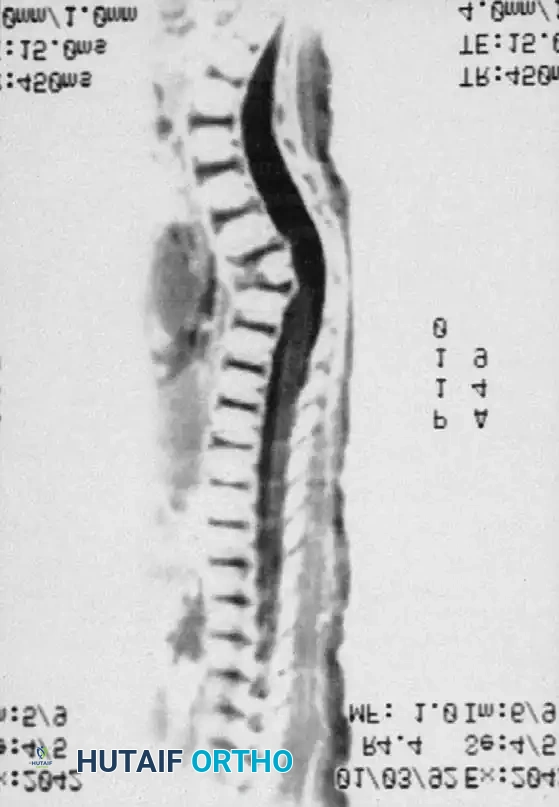

3. Magnetic Resonance Imaging (MRI):

MRI is the gold standard for evaluating the neural elements. It identifies the exact location of the spinal cord relative to the bony apex, highlights areas of cord compression or myelomalacia, and detects associated intraspinal anomalies (e.g., diastematomyelia, tethered cord, syringomyelia). MRI also clearly defines the unossified cartilage anlage in young children.

MRI of type I congenital kyphosis